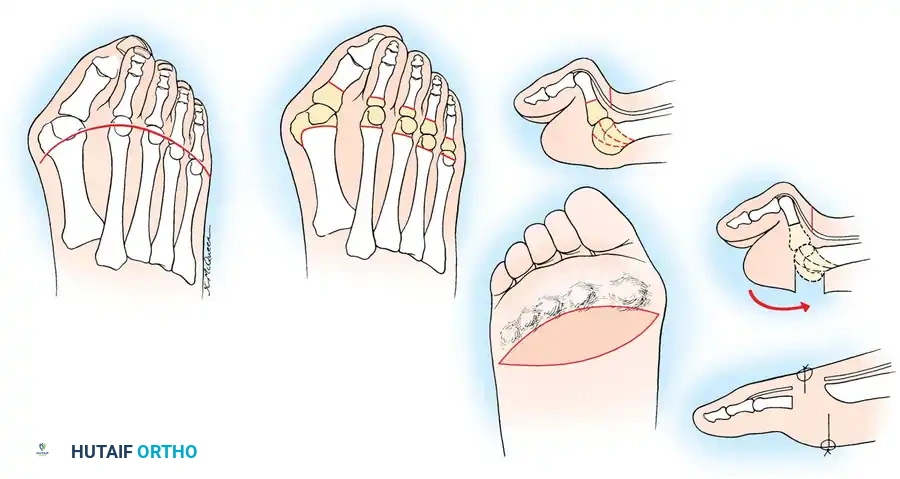

القدم والكاحل

آلام القدم المزمنة؟ اكتشف الأسباب والعلاج قبل فوات الأوان